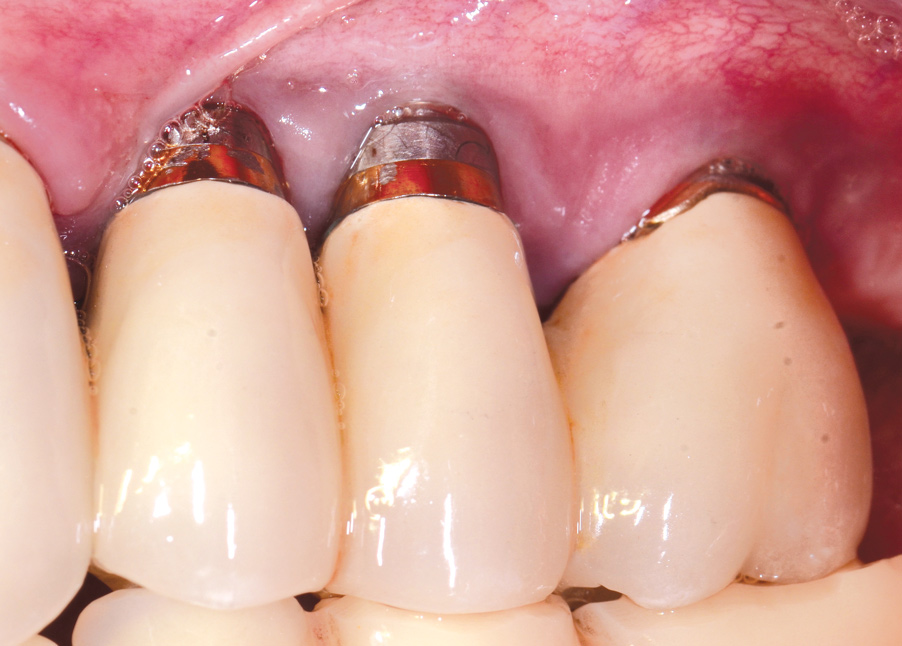

Dental implants have revolutionized the way in which clinicians treat and restore partially and fully edentulous patients and have demonstrated success for managing a broad range of clinical dilemmas. While implants have been highly predictable and have achieved long-term success, they are not immune from complications associated with improper treatment planning, poor surgical and prosthetic execution, material failure, and inadequate or infrequent maintenance. Among these problems are the biologic complications of peri-implant mucositis and peri-implantitis, which are inflammatory conditions in the soft and/or hard tissues surrounding dental implants (Figure 1 through Figure 4).1,2

Fig 1. Clinical view of severe gingival inflammation with possible early bone loss present around the implant at the site of the maxillary left first molar. The two premolar implants had mucogingival deformities.

Figure 1